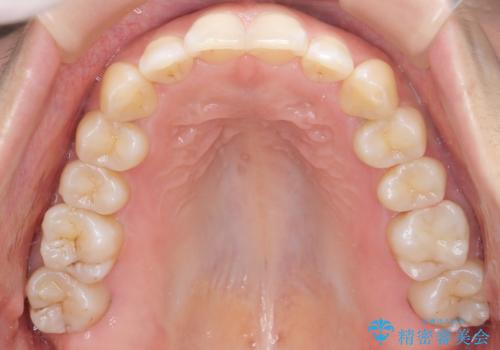

下の前歯のがたつき インビザラインで

- 前歯のがたつきを主訴に来院。

インビザラインで上下の前歯をわずかに削って並べました。

下の歯の叢生を並べると多少ブラックトライアングルがでることがあります。